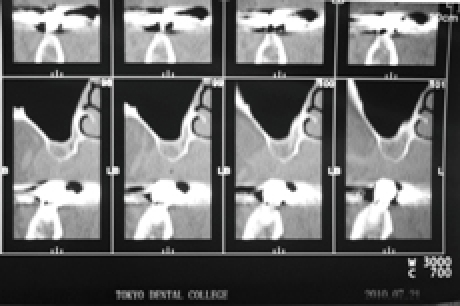

非常に薄い骨(CTで確認)につきインプラント困難ケース。口蓋を覆う義歯がどうしてもなじめないため、インプラント2本を用いて特殊な義歯での治療をおこなうことに。

このケースは、骨があまりに薄くて上顎洞側壁が、ピンセットで簡単に剥がれるほどでした。ラテラルウインドテクニックですが、いつも10~15mmぐらいの穴で、極力歯肉を剥がさずおこなっております。(術後の腫れを少なくするため。)